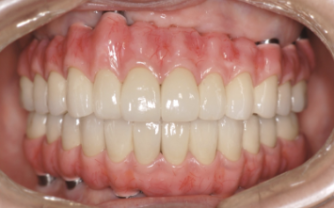

| 主訴 | 全顎治療希望、全顎的に歯が動く、奥の歯がなくて噛めない。できるだけ綺麗で噛めるようになりたい。 |

| 治療内容 | 全顎的に歯周病、前歯部の被蓋が深く、重度歯列不正が認められるため、 歯周外科を含む歯周治療、矯正治療、インプラント治療、セラミックによる補綴治療後メインテナンスに移行しました。 |

| 治療費 | 5,060,000円(税込)(インプラントすべて含む) |

| 治療期間 | 2年4ヶ月 |

| 治療回数 | 90回 |

| 想定されたリスク | 矯正治療の後戻り、歯周病の再発、食いしばり(パラファンクション)によるセラミックの破折、歯の破折のリスクがありました。 |